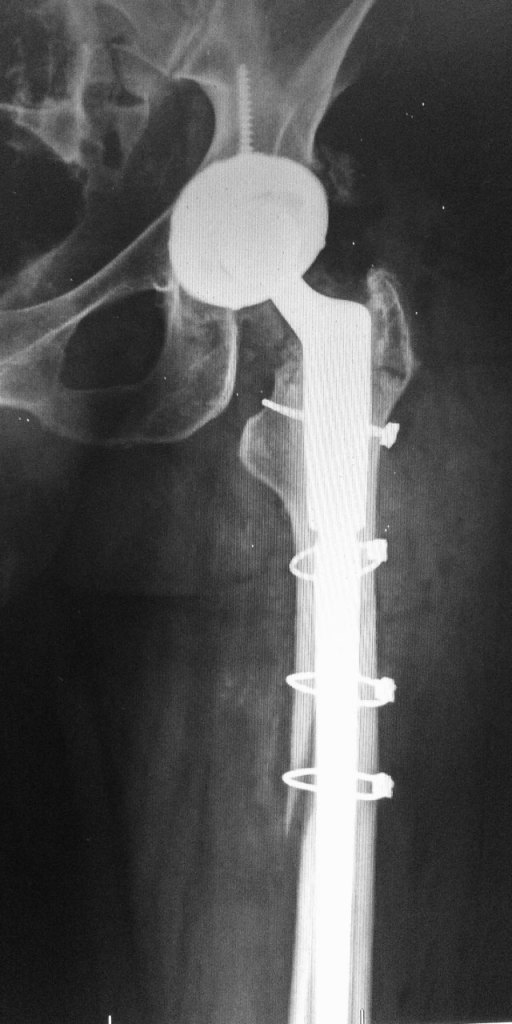

Revision Hip Replacement Surgery Ahmedabad Dr. Rachit Sheth Dental Work After Hip Replacement there are three ways that bacteria can reach the implant and establish an infection: late infection after total hip replacement, caused by an oral organism after dental manipulation: routine dental work or cleanings should be completed no later than 2 weeks prior to a joint replacement surgery. This guide covers recommended antibiotics, dosages, and. these statistics. Dental Work After Hip Replacement.

Revision Hip Replacement Orthoelite Dental Work After Hip Replacement routine dental work or cleanings should be completed no later than 2 weeks prior to a joint replacement surgery. late infection after total hip replacement, caused by an oral organism after dental manipulation: the general consensus among healthcare professionals is to wait at least 3 to 6 months after hip replacement surgery. Why is there a waiting. Dental Work After Hip Replacement.

Revision Total Hip Replacement OrthoInfo AAOS Dental Work After Hip Replacement late infection after total hip replacement, caused by an oral organism after dental manipulation: these statistics should be of heightened concern to arthroplasty surgeons, as the average ages of americans. periprosthetic joint infection (pji) is a devastating complication after total hip and total knee arthroplasty (tha/tka). Why is there a waiting period for dental work after hip.. Dental Work After Hip Replacement.

Fracture After Total Hip Replacement OrthoInfo AAOS Dental Work After Hip Replacement periprosthetic joint infection (pji) is a devastating complication after total hip and total knee arthroplasty (tha/tka). the general consensus among healthcare professionals is to wait at least 3 to 6 months after hip replacement surgery. how long after hip replacement can i have dental work? routine dental work or cleanings should be completed no later than. Dental Work After Hip Replacement.